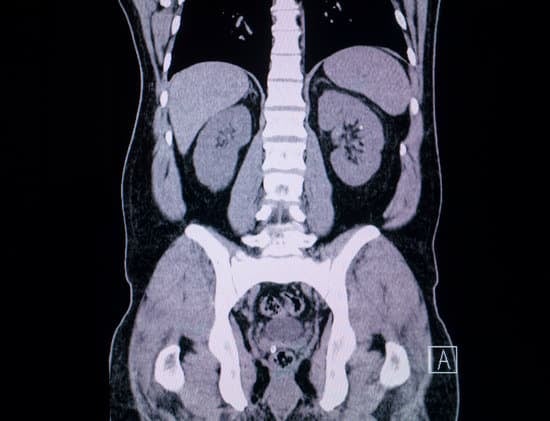

CT 대장조영술(CT Colonography, 가상 대장내시경)은 컴퓨터 단층 촬영(CT)을 활용하여 대장 내부를 3D 이미지로 재구성하는 비침습적 검사 방법입니다.

내시경을 직접 삽입하지 않고, 대장의 구조와 용종의 유무를 파악할 수 있어 환자에게 불편함이 적습니다.

CT 촬영 시 3D 이미지가 생성되며, 이를 분석하여 대장 내부를 시각적으로 확인합니다.

컴퓨터 소프트웨어가 촬영된 이미지를 3차원으로 재구성하여 마치 내시경을 삽입한 것처럼 대장 내부를 확인할 수 있습니다.

대장 외 다른 질환 발견 가능

대장뿐만 아니라 주변 장기의 상태도 확인할 수 있습니다.